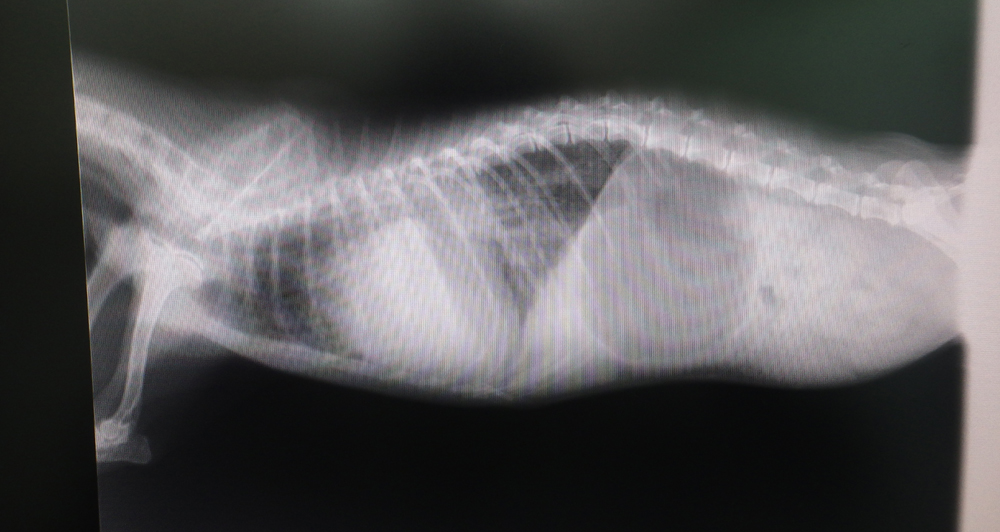

重症になるとうっ血性心不全を起こして、肺に水がたまったり(肺水腫)、呼吸状態が悪くなったりして、失神を起こしたりすることもあります。

うっ血性心不全や肺水腫を起こしている場合には、入院で酸素室管理や利尿剤の投与などを行います。